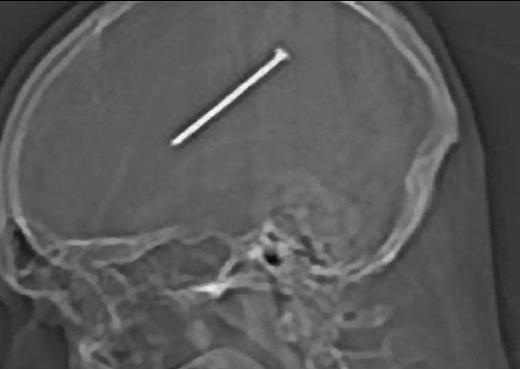

3. Bu CT scan görüntüsü ise Brezilyalı Emerson de Oliveira Abreu'ye ait. Sualtında balık tutmaya çalışırken kaza sonucu kafasına zıpkın saplanan Abreu, doktorların başarılı operasyonu sonucu kurtarıldı.

Bu CT scan görüntüsü ise Brezilyalı Emerson de Oliveira Abreu'ye ait. Sualtında balık tutmaya çalışırken kaza sonucu kafasına zıpkın saplanan Abreu, doktorların başarılı operasyonu sonucu kurtarıldı.